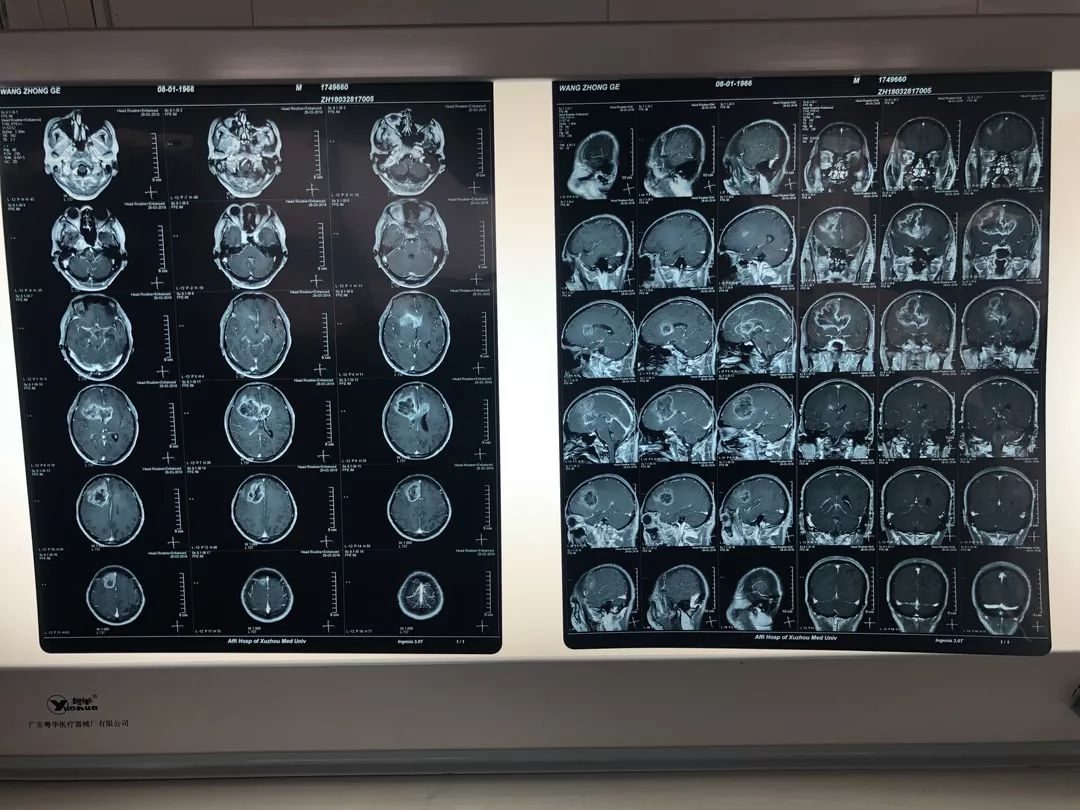

徐医附院脑科医院院长、神经外科主任于如同教授介绍说,王先生的胶质瘤比较大,前来就诊的时候,精神很淡漠,肢体活动也很差,呈嗜睡状态,后来做检查之后,发现病人在胼胝体部位、在脑子额叶中间胼胝体部位有一个比较大的肿瘤——直径超过10公分,并且它是弥漫性生长,肿瘤生长的边界也是不清楚的,它已经侵犯到正常脑组织里去了。

王先生就诊几天后,徐医附院神经外科团队为王先生成功地实施了胶质瘤切除手术。手术很成功,术后王先生恢复情况也比较好。从复查的CT片看,肿瘤已全部切除,并且神经血管都保护得很好,所以下手术台时病人的神志都是清楚的,精神状况也比术前好很多。